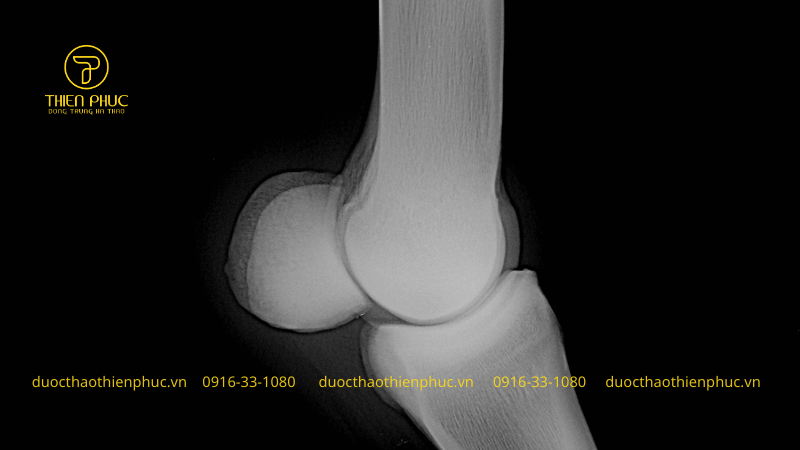

Chondroitin là một dạng glycosaminoglycan. Tồn tại tự nhiên trong sụn khớp của con người. Đây là thành phần quan trọng giúp duy trì độ đàn hồi và chắc khỏe của khớp. Ngăn ngừa tổn thương sụn do lão hóa hoặc tác động cơ học. Nhờ khả năng hút nước và giữ nước tốt, chondroitin giúp bôi trơn các khớp. Giảm ma sát khi vận động và bảo vệ khớp khỏi các tác động tiêu cực.

Hỗ trợ tái tạo sụn khớp

Chondroitin kích thích sản sinh collagen và proteoglycan, hai thành phần thiết yếu của sụn khớp. Nhờ vậy, hợp chất này giúp tăng cường khả năng tự phục hồi của sụn. Làm chậm quá trình hao mòn do tuổi tác hoặc vận động mạnh.

Phòng ngừa thoái hóa khớp

Bổ sung chondroitin giúp duy trì độ đàn hồi và bôi trơn khớp. Từ đó hạn chế tình trạng khô khớp và thoái hóa sụn. Đây là giải pháp hữu ích cho những người trên 40 tuổi hoặc những ai thường xuyên vận động mạnh như vận động viên, người lao động chân tay.